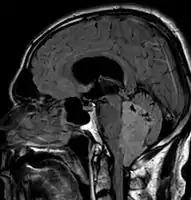

An ependymoma is a tumor that arises from the ependyma, a tissue of the central nervous system. Usually, in pediatric cases the location is intracranial, while in adults it is spinal. The common location of intracranial ependymomas is the fourth ventricle. Rarely, ependymomas can occur in the pelvic cavity.

Ependymomas make up about 5% of adult intracranial gliomas and up to 10% of childhood tumors of the central nervous system (CNS). Their occurrence seems to peak at age 5 years and then again at age 35. They develop from cells that line both the hollow cavities of the brain and the canal containing the spinal cord, but they usually arise from the floor of the fourth ventricle, situated in the lower back portion of the brain, where they may produce headache, nausea and vomiting by obstructing the flow of cerebrospinal fluid. This obstruction may also cause hydrocephalus. They may also arise in the spinal cord, conus medullaris and supratentorial locations.[4] Other symptoms can include (but are not limited to): loss of appetite, difficulty sleeping, temporary inability to distinguish colors, uncontrollable twitching, seeing vertical or horizontal lines when in bright light, and temporary memory loss. It should be remembered that these symptoms also are prevalent in many other illnesses not associated with ependymoma.

Although some ependymomas are of a more anaplastic and malignant type, most of them are not anaplastic. Well-differentiated ependymomas are usually treated with surgery. For other ependymomas, total surgical removal is the preferred treatment in addition to radiation therapy. The malignant (anaplastic) varieties of this tumor, malignant ependymoma and the ependymoblastoma, are treated similarly to medulloblastoma but the prognosis is much less favorable. Malignant ependymomas may be treated with a combination of radiation therapy and chemotherapy. Ependymoblastomas, which occur in infants and children younger than 5 years of age, may spread through the cerebrospinal fluid and usually require radiation therapy. The subependymoma, a variant of the ependymoma, is apt to arise in the fourth ventricle but may occur in the septum pellucidum and the cervical spinal cord. It usually affects people over 40 years of age and more often affects men than women.[7]